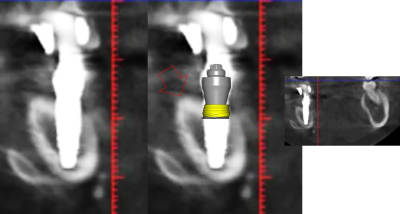

1 se baser sur la pano pour en tirer des conclusions est une erreur de débutant

2 sur les coupes scanner une partie du col est infra osseuse et l'autre non

3 lorsque tu te permets le genre de commentaire que tu fais il faut être en mesure d'étayer un argumentaire

> 1 se baser sur la pano pour en tirer des conclusions est une erreur de débutant

>

> 2 sur les coupes scanner une partie du col est infra osseuse et l'autre non